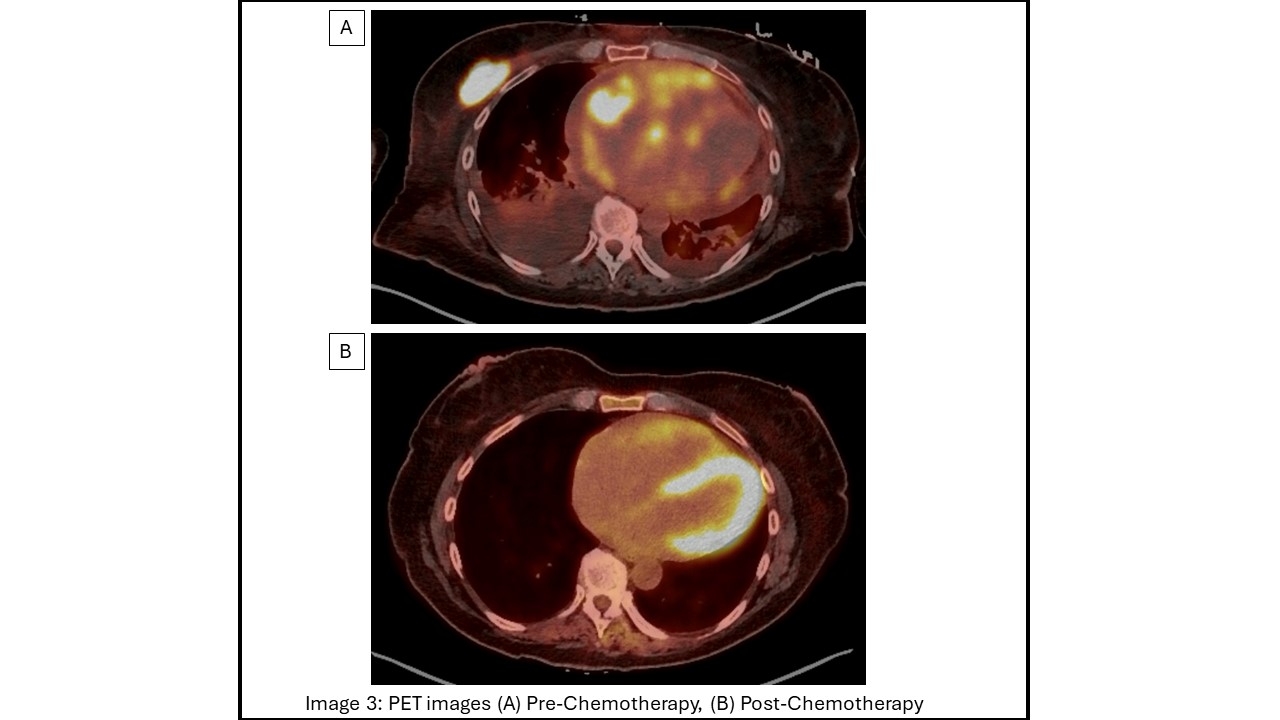

Traditionally, DLBCL is treated with R-CHOP (Rituximab, Cyclophosphamide, Doxorubicin, Vincristine, Prednisone), however up to 40% of patients develop refractory disease or have a relapse1. As in the recent POLARIX trial1, our patient underwent three cycles of novel regimen of Pola-R-CHP. Follow up PET showed dramatic response with metabolic remission (Image 3). Cardiac MRI showed reduction in RV tumor, RA thrombus and inflammatory burden with preserved LV and RV function (Image 2). No further arrhythmias were noted and the patient completed chemotherapy. This case highlights a positive outcome in a patient with aggressive DLBCL with cardiac metastasis treated with Polatuzumab based therapy.